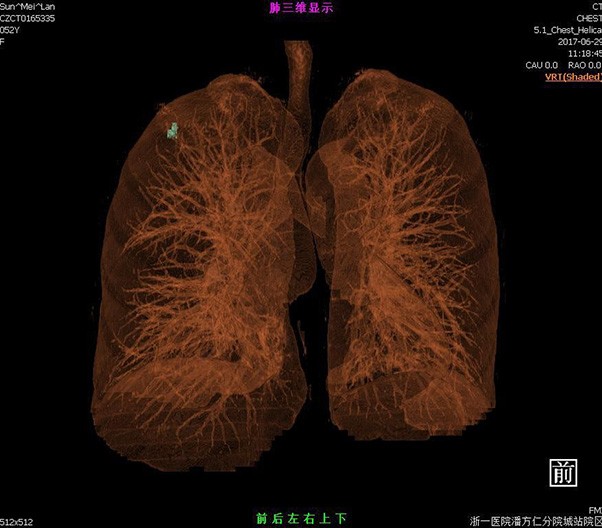

Lung reverse scanning eliminate respiratory motion artifact

臨床畫廊